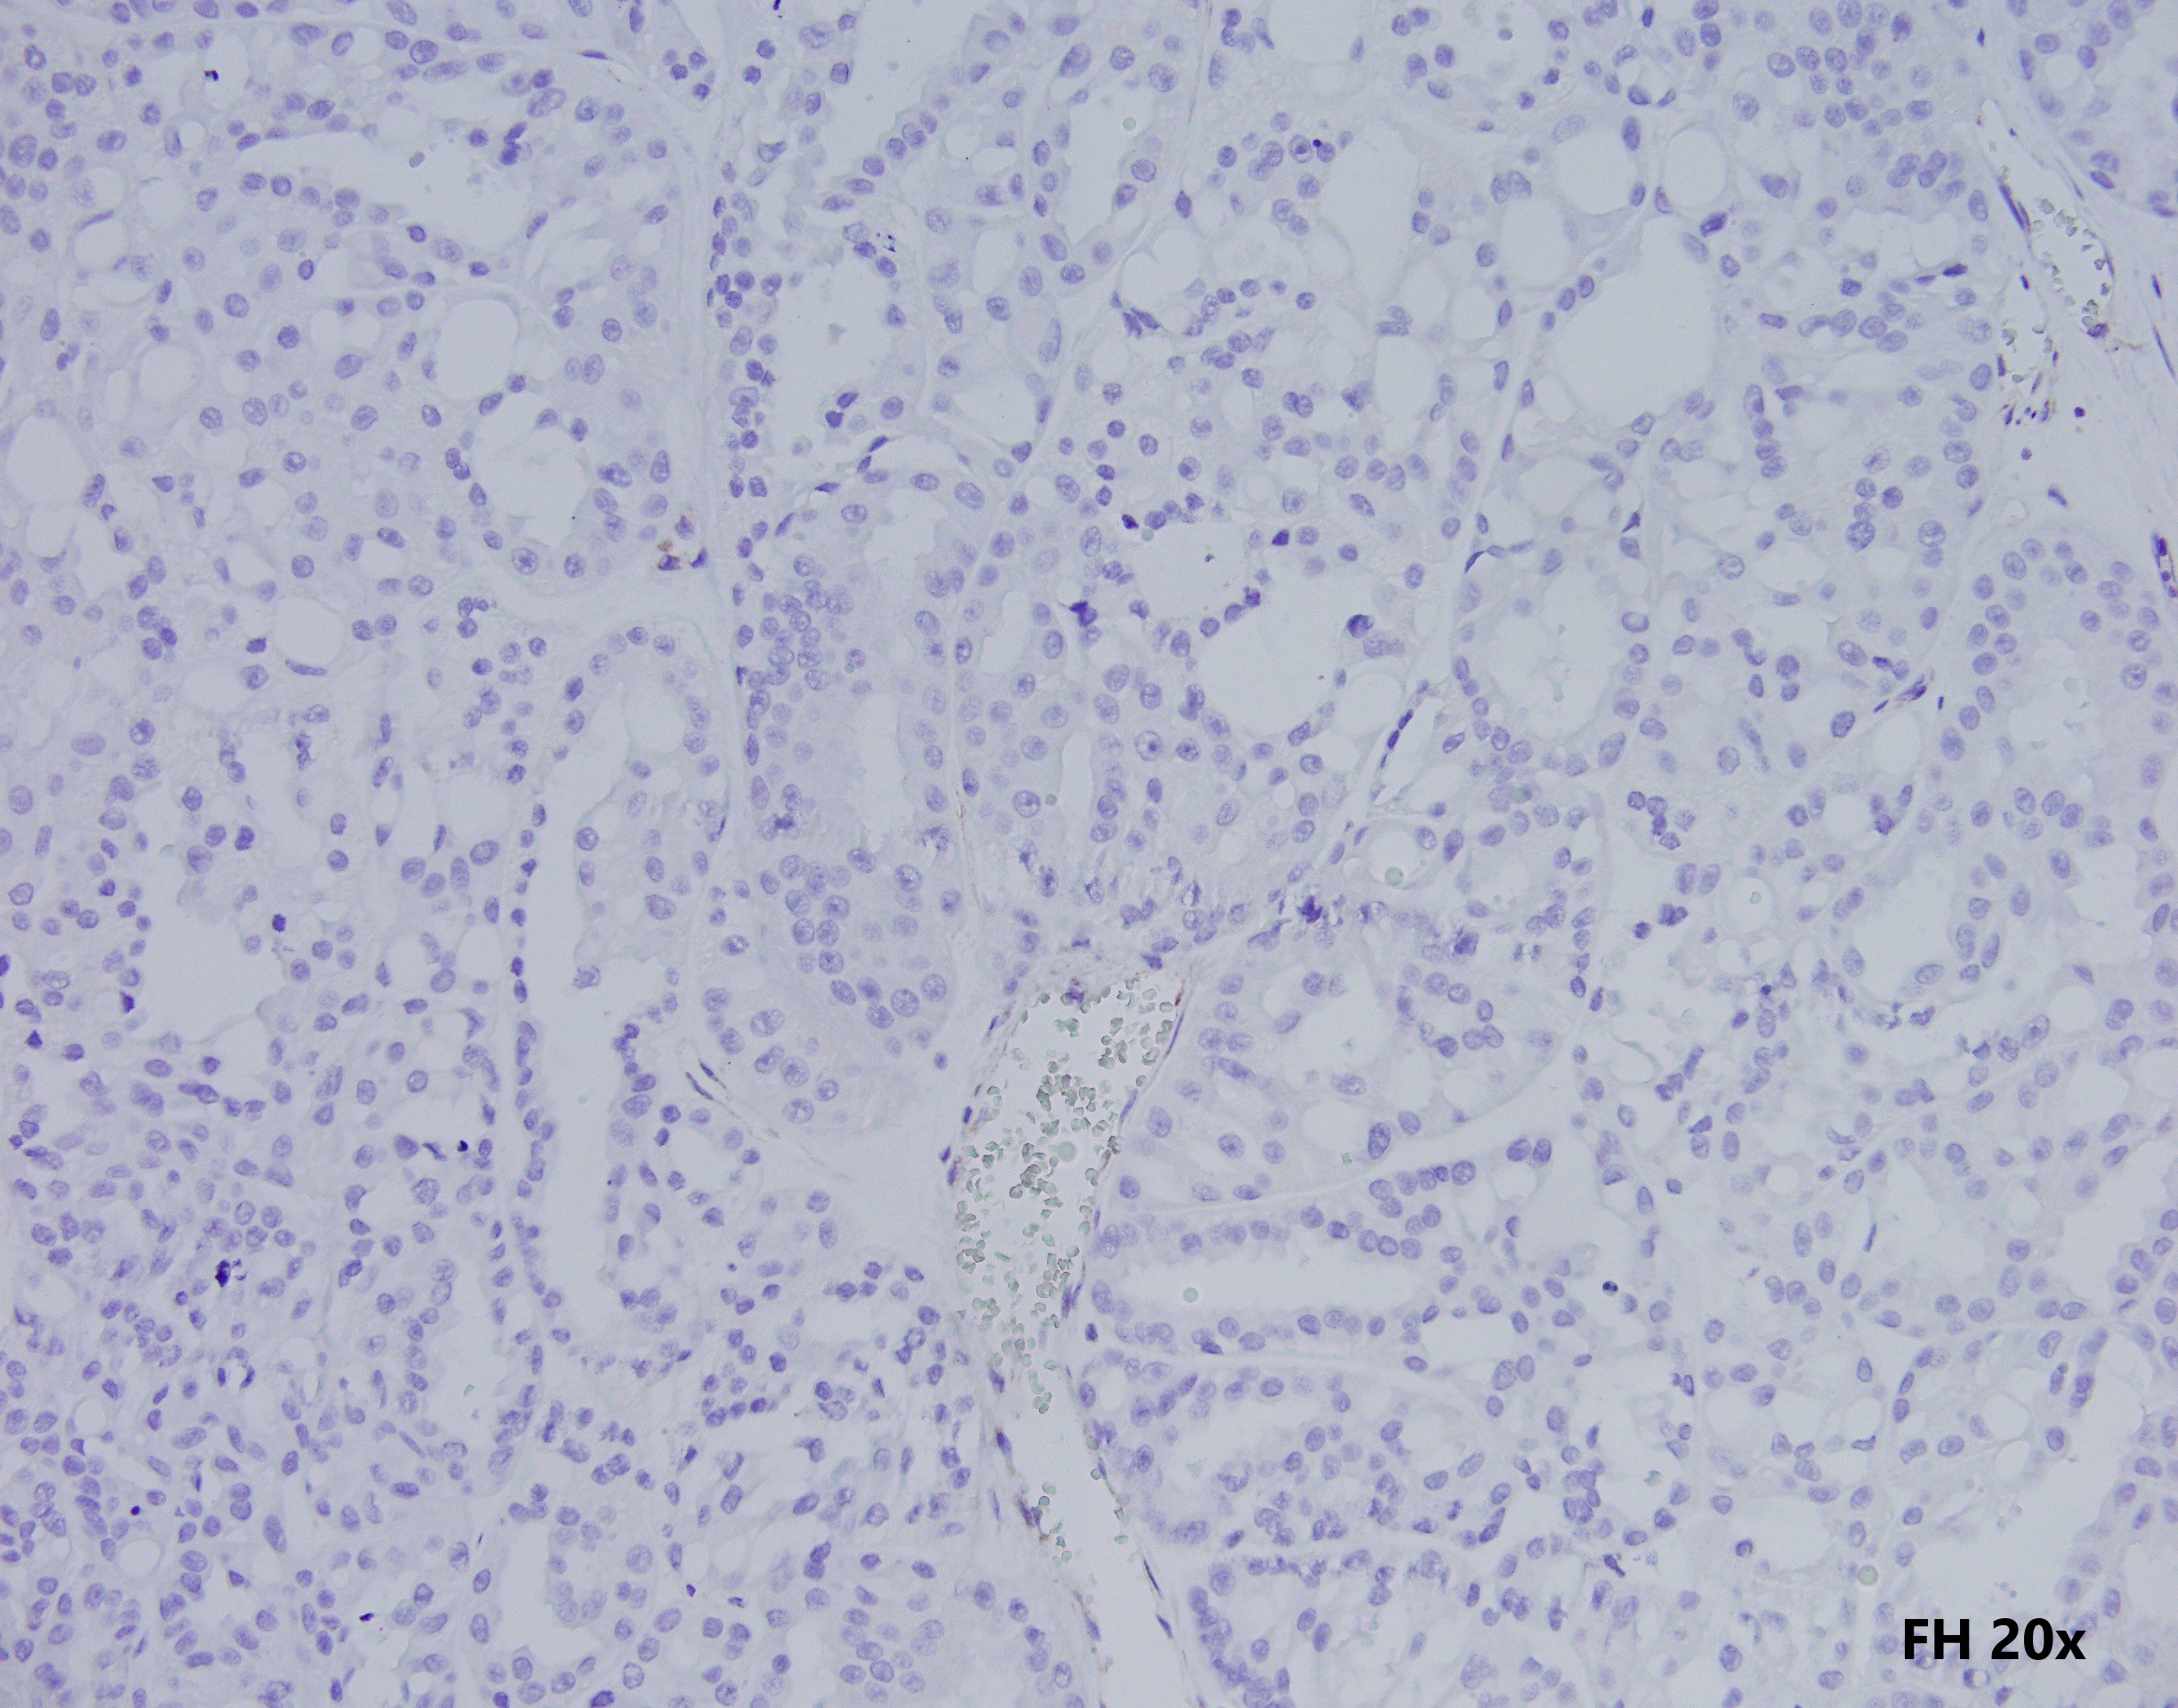

35 year-old-male with an 8 cm well-circumscribed, solid mass located in the upper pole of the left kidney with associated para-aortic metastasis. H&E, and IHC stains are shown.

Histologically, FH-deficient RCCs were originally described as type 2 papillary RCC and occasionally as collecting duct carcinoma (CDC), with a spectrum of architectural patterns including papillary, tubulopapillary, tubular, cribriform, solid and cystic elements. The morphological hallmarks of HLRCC are characteristic nuclear features: a large nucleus with a very prominent inclusion-like eosinophilic nucleolus surrounded by a perinucleolar halo. Based on these architectural and nuclear features, the differential diagnosis of HLRCC could include a variety of high-grade RCCs of different histological subtypes, particularly type 2 papillary RCC, CDC, or high-grade RCC, unclassified. Recently, an expanded histological spectrum of FH-deficient RCC has been described, including tubulocystic carcinoma with poorly differentiated foci, and SDH-deficient RCC like morphology was observed in FH-deficient RCC.

These tumours are characterised by negative immunohistochemistry for FH and aberrant succination of cellular proteins (2-succinylcysteine, 2SC). However, not all RCC show loss of FH stain by IHC (choice c is not right).